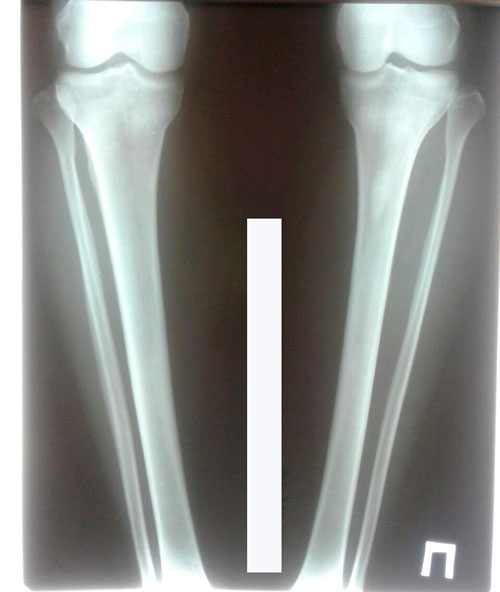

Дата операции 15.01.2018г.

Дата снятия аппаратов 23.04.2018г.

Срок лечения 97 дней.